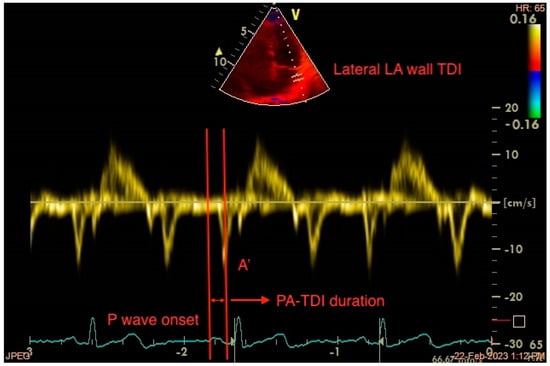

4.2. Total Atrial Conduction Time (PA-TDI Duration)

- Müller, P.; Weijs, B.; Bemelmans, N.M.A.A.; Mügge, A.; Eckardt, L.; Crijns, H.J.G.M.; Bax, J.J.; Linz, D.; den Uijl, D.W. Echocardiography-Derived Total Atrial Conduction Time (PA-TDI Duration): Risk Stratification and Guidance in Atrial Fibrillation Management. Clin. Res. Cardiol. 2021, 110, 1734–1742. [Google Scholar] [CrossRef] [PubMed]

- Müller, P.; Hars, C.; Schiedat, F.; Bösche, L.I.; Gotzmann, M.; Strauch, J.; Dietrich, J.W.; Vogt, M.; Tannapfel, A.; Deneke, T.; et al. Correlation Between Total Atrial Conduction Time Estimated via Tissue Doppler Imaging (PA-TDI Interval), Structural Atrial Remodeling and New-Onset of Atrial Fibrillation After Cardiac Surgery: The Role of Total Atrial Conduction Time in Patients Undergoing Cardiac Surgery. J. Cardiovasc. Electrophysiol. 2013, 24, 626–631. [Google Scholar]

- De Vos, C.B.; Weijs, B.; Crijns, H.J.G.M.; Cheriex, E.C.; Palmans, A.; Habets, J.; Prins, M.H.; Pisters, R.; Nieuwlaat, R.; Tieleman, R.G. Atrial Tissue Doppler Imaging for Prediction of New-Onset Atrial Fibrillation. Heart 2009, 95, 835–840. [Google Scholar] [CrossRef]

- Özlü, M.F.; Erdem, K.; Kırış, G.; Parlar, A.İ.; Demirhan, A.; Ayhan, S.S.; Erdem, A.; Öztürk, S.; Tekelioğlu, Ü.Y.; Yazıcı, M. Predictive Value of Total Atrial Conduction Time Measured with Tissue Doppler Imaging for Postoperative Atrial Fibrillation after Coronary Artery Bypass Surgery. J. Interv. Card. Electrophysiol. 2013, 37, 27–33. [Google Scholar] [CrossRef] [PubMed]

- Müller, P.; Schiedat, F.; Dietrich, J.-W.; Shin, D.-I.; Kara, K.; Mügge, A.; Deneke, T. Reverse Atrial Remodeling in Patients Who Maintain Sinus Rhythm after Electrical Cardioversion: Evidence Derived from the Measurement of Total Atrial Conduction Time Assessed by PA-TDI Interval. J. Echocardiogr. 2014, 12, 142–150. [Google Scholar] [CrossRef] [PubMed]

- Chao, T.-F.; Lin, Y.-J.; Tsao, H.-M.; Chang, S.-L.; Lo, L.-W.; Hu, Y.-F.; Tuan, T.-C.; Li, C.-H.; Chang, H.-Y.; Wu, T.-J.; et al. Prolonged Atrium Electromechanical Interval Is Associated with Stroke in Patients with Atrial Fibrillation After Catheter Ablation. J. Cardiovasc. Electrophysiol. 2013, 24, 375–380. [Google Scholar] [CrossRef]

- Tjahjadi, C.; Hiemstra, Y.L.; van der Bijl, P.; Pio, S.M.; Bootsma, M.; Ajmone Marsan, N.; Delgado, V.; Bax, J.J. Assessment of Left Atrial Electro-Mechanical Delay to Predict Atrial Fibrillation in Hypertrophic Cardiomyopathy. Eur. Heart J. Cardiovasc. Imaging 2021, 22, 589–596. [Google Scholar] [CrossRef]

- Erdem, F.H.; Erdem, A.; Özlü, F.; Ozturk, S.; Ayhan, S.S.; Çağlar, S.O.; Yazici, M. Electrophysiological Validation of Total Atrial Conduction Time Measurement by Tissue Doppler Echocardiography According to Age and Sex in Healthy Adults. J. Arrhythmia 2016, 32, 127–132. [Google Scholar] [CrossRef]